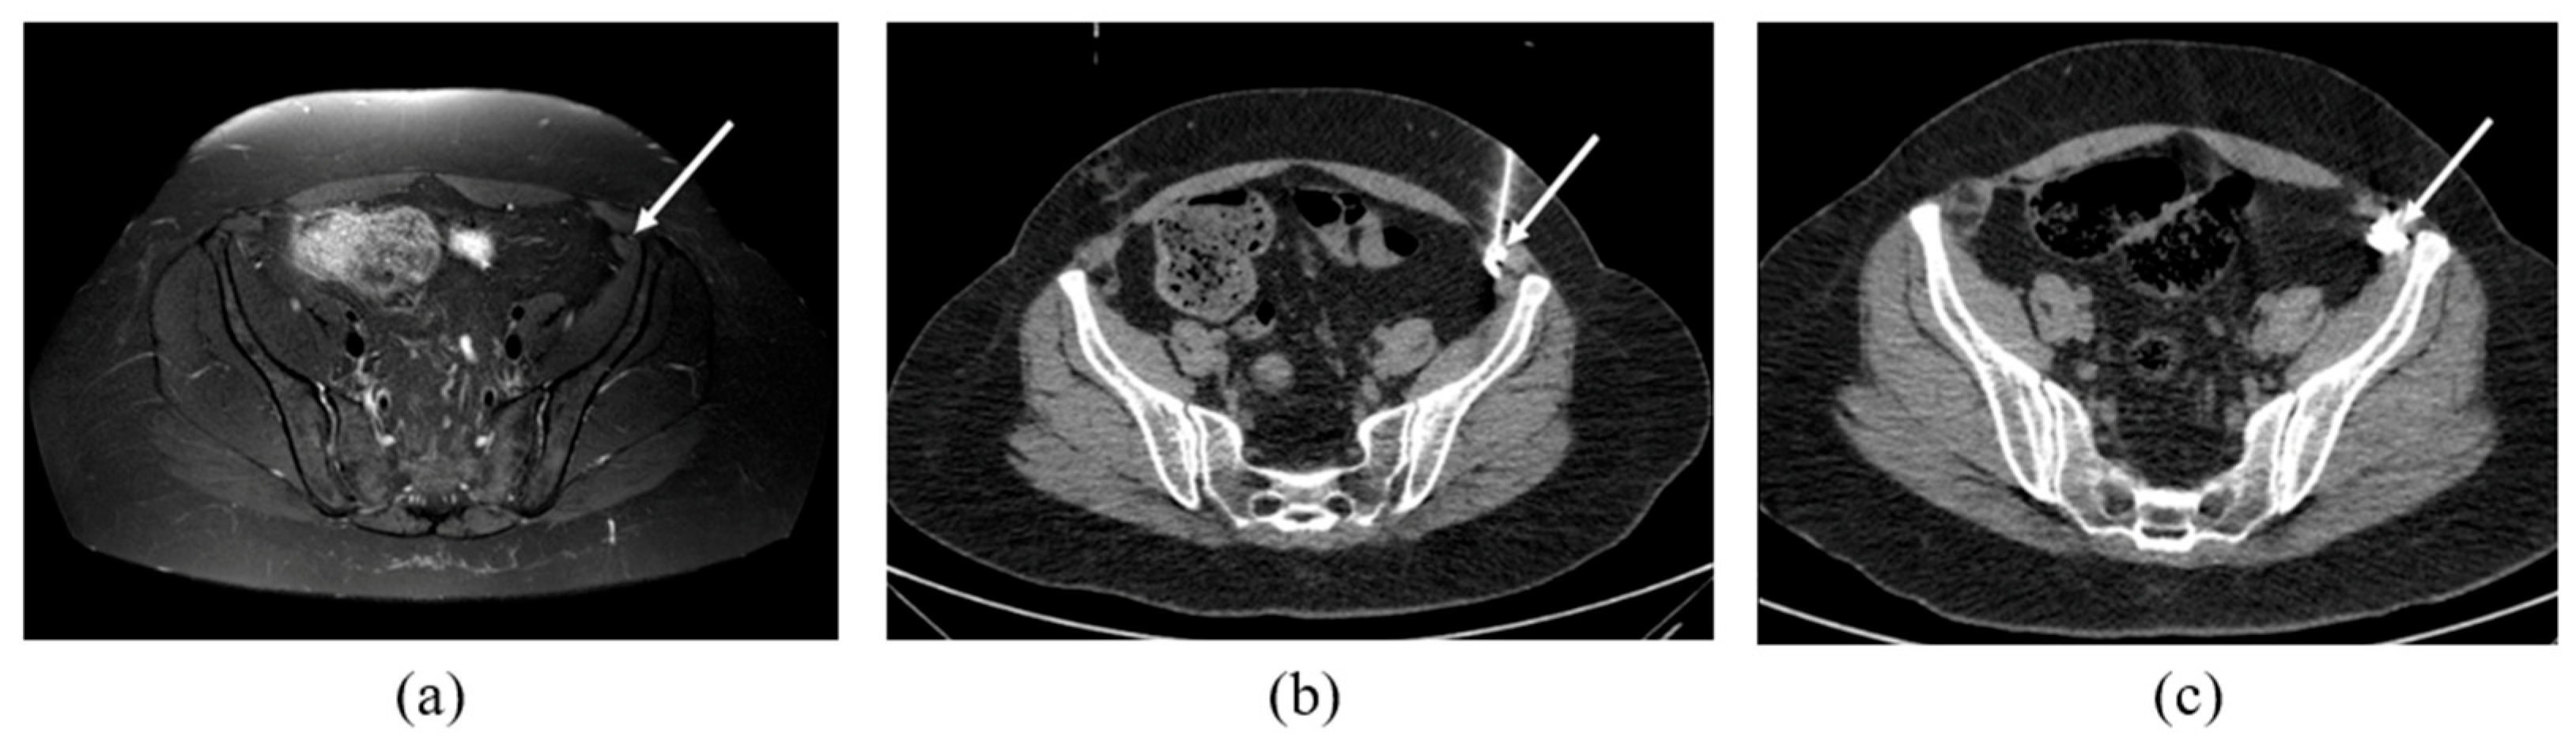

2.2. CT-Guided Procedures

3.2. MRN Findings